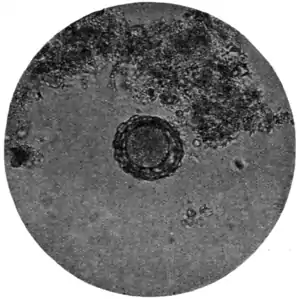

Fig. 171.—Ovum of A. lumbricoides, x 250. (Photograph by Dr. J. Bell.)

The ova of Ascaris lumbricoides (Fig. 168, f, g, and Fig. 171) are considerably larger (60 to 75 μ by 40 to 58 μ) than those of trichiuris (Fig. 168, c). They are also, as a rule, more spherical, or rather, more broadly oval; occasionally they are almost barrel-shaped. Like those of trichocephalus, they are dark brown in colour from bile-staining, but they are much less sharply and smoothly defined, possessing a coarse thick shell which is roughened by many warty excrescences. The yolk contents are not always easily made out, nor, when made out, can any sign of embryo or segmentation be discovered.

In certain instances, supposed to be unfertilized, the ova are smooth on the surface, the rough outer layer being almost or altogether absent.

A point of practical importance to be attended to lies in the circumstance that the rough outer layer on the shell of the ovum of ascaris is very easily detached, leaving the egg with a sharp, smooth outline suggestive of some other species of parasite. To obviate this, in mounting fæces it is well to avoid too much gliding of the cover-glass over the slip.